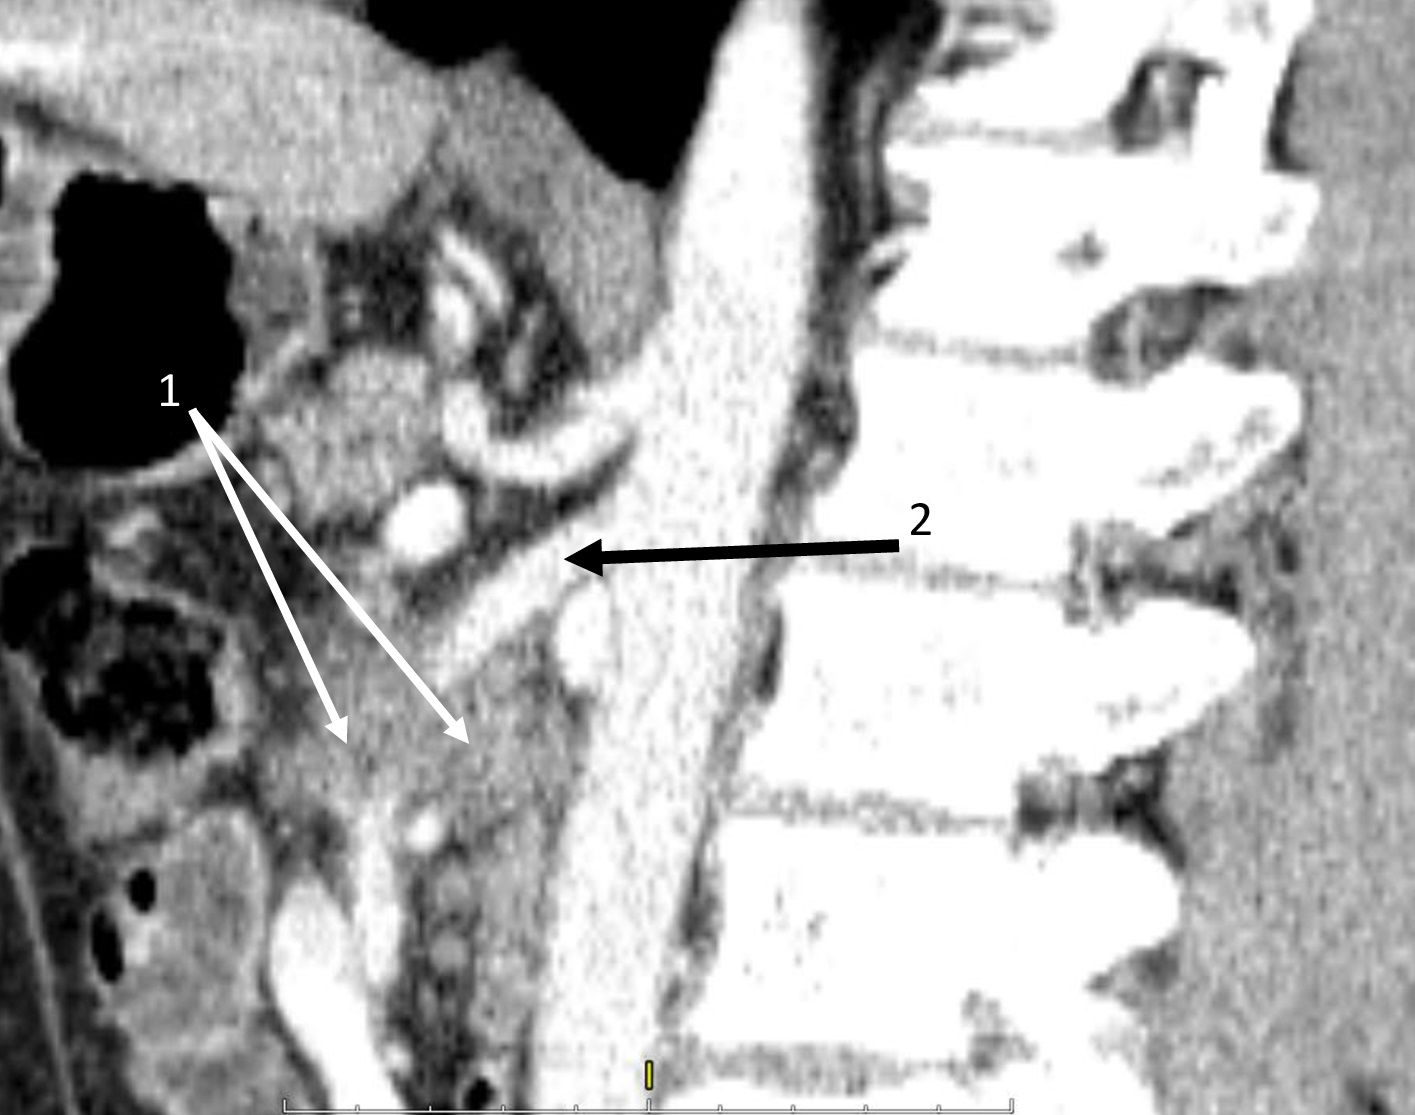

|  | 2. Состояние опухоли до начала неоадъювантной терапии. | |

| Тема | ||

| Тип | Исследовательские инструменты | |

|

Посмотреть

(220KB)

| Метаданные ▾ | |